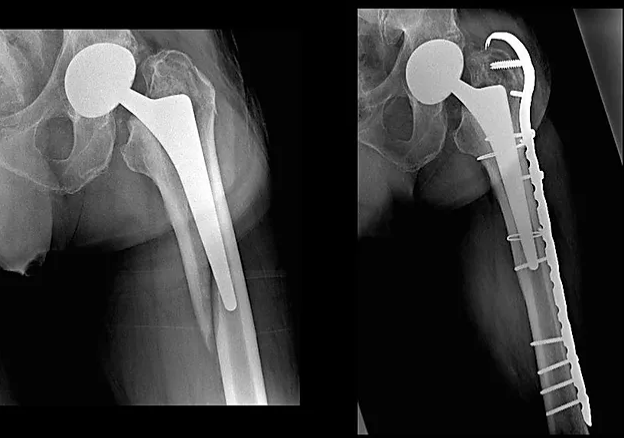

Il giorno 16 dicembre 2019 viene eseguito intervento chirurgico di Revisione, osteosintesi con placca ad uncino e sostituzione stelo, periodo post operatorio trascorso in maniera ottimale.

- In 40° giornata la deambulazione con una sola stampella e si esegue la RX di controllo e la visita ortopedica.

- radiografia di controllo per valutare il callo osseo e l’impianto dei fissatori.